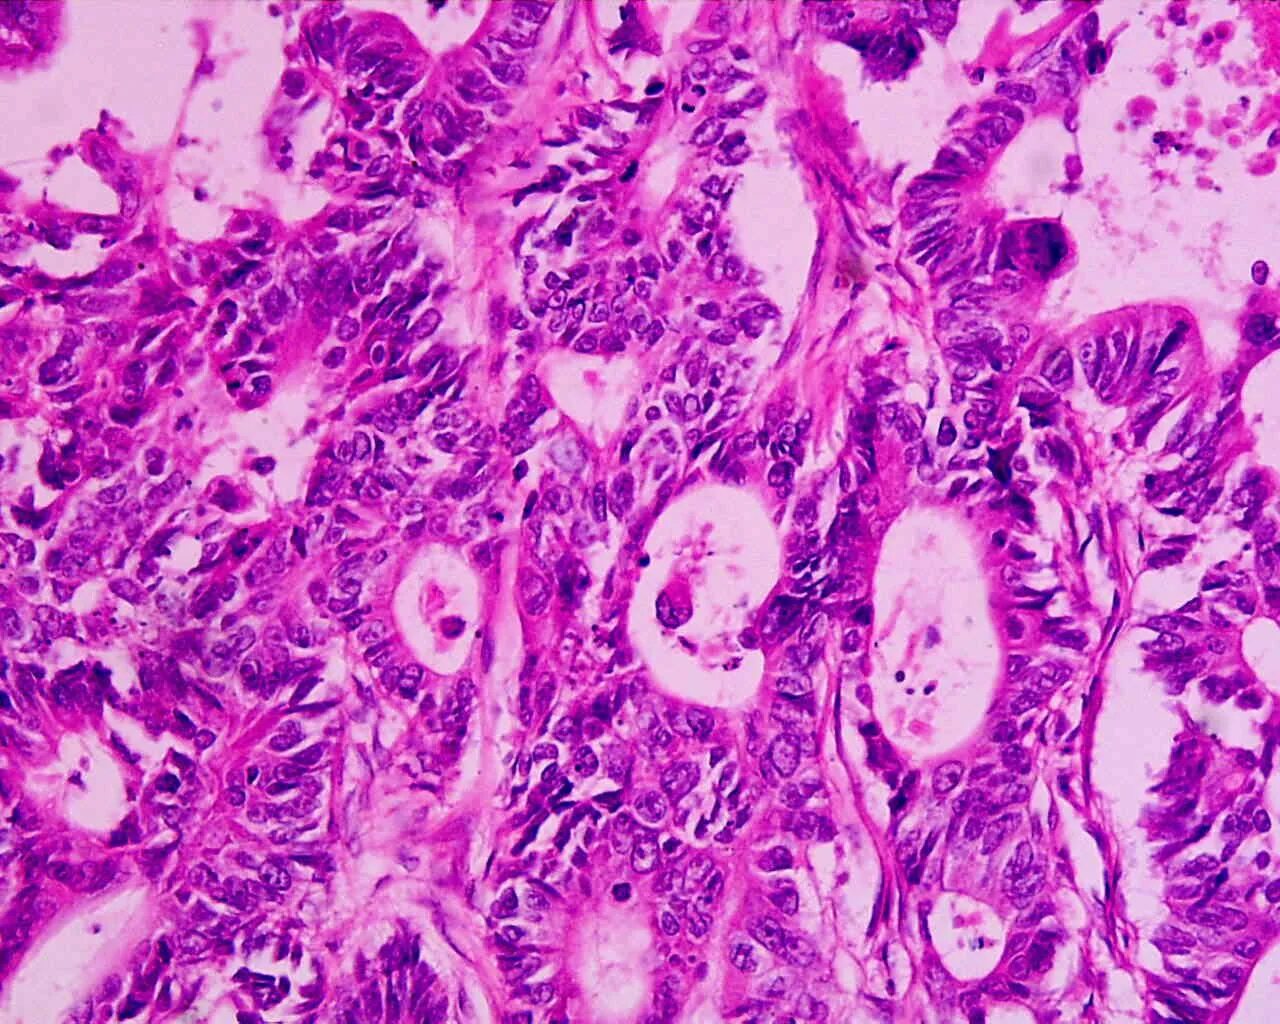

Что значит умеренно дифференцированная аденокарцинома